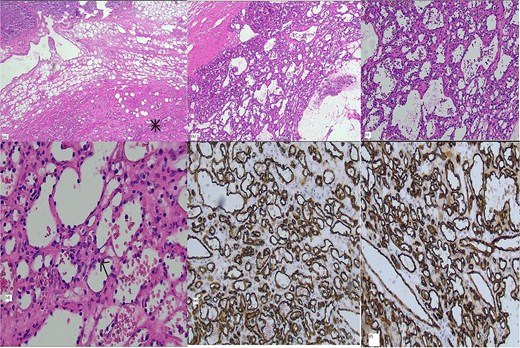

Patient underwent a laparoscopic left adrenalectomy a few months after investigations. He had an uneventful surgery with an area of tissue adhesion at the renal margin. The histology reveals a circumscribed, non-encapsulated lesion in the periadrenal fat, characterized by irregular, anastomosing capillary-sized spaces lined by a single layer of endothelial cells with hobnail morphology. There is no nuclear atypia or mitotic activity. The surrounding stroma is edematous, with areas of fibrous and hemorrhagic cystic degeneration. Immunohistochemical staining for CD31 and CD34 confirms the endothelial nature of the lesion, leading to a diagnosis of anastomosing hemangioma. Clear margins were achieved during resection. The patient was discharged the following day after overnight monitoring. A follow-up appointment in the outpatient department three weeks post-surgery confirmed the patient was recovering well.

It is commonly diagnosed postoperatively by histologic examination, which requires differentiation from aggressive angiosarcoma. Grossly, they are well-circumscribed hemorrhagic lesions and histologically show prominent hobnailing of endothelial cells with anastomosing sinusoidal spaces without evidence of atypia or invasive malignancy. Recent retrospective study of 13 anastomosing hemangiomas showed GNAQ gene mutation as a driver for pathogenesis of anastomosing hemangioma, which is not found in angiosarcoma [5]. This could potentially be useful in preoperative biopsy to distinguish from angiosarcoma (Fig. 2).

Histology: (a) Hematoxylin and eosin (H&E) stain × 2 magnification showing interface of adrenal (top) and vascular lesion (bottom), (b) H&E stain × 4 magnification (c) H&E stain × 10 magnification, (d) H&E stain × 20 magnification, positive vascular endothelial immunohistochemical markers CD 31 (e) and CD 34 (f).